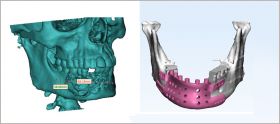

3D Incredible Medical is the only metal 3d printing company in India. We use the latest Metal 3D printing (Additive Manufacturing) manufacturing technology. With this latest manufacturing process, the parts are built very close to the required dimensions with an accuracy of 0.2 mm. 3D Incredibles Medical specializes in manufacturing various Maxillofacial Designs, ortho implants solutions , Anatomy Model, and many more.

Maxillofacial Designs By 3D Incredible for Maxillofacial Prosthetics